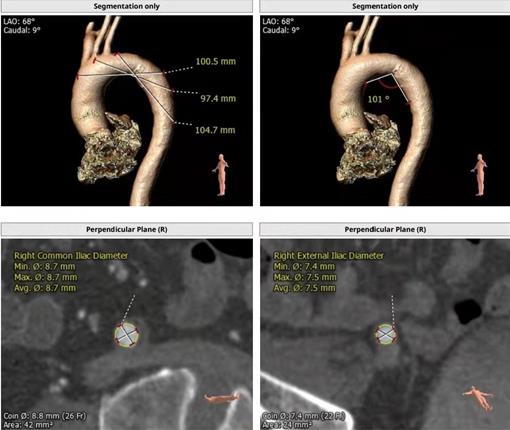

術(shù)前CTA評(píng)估